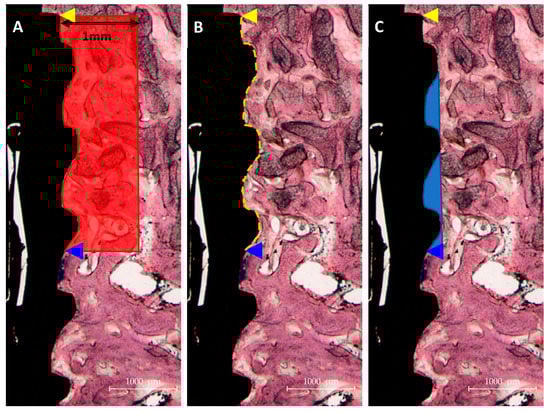

3.2.3. Histological Findings

3.2.4. Histometric Findings